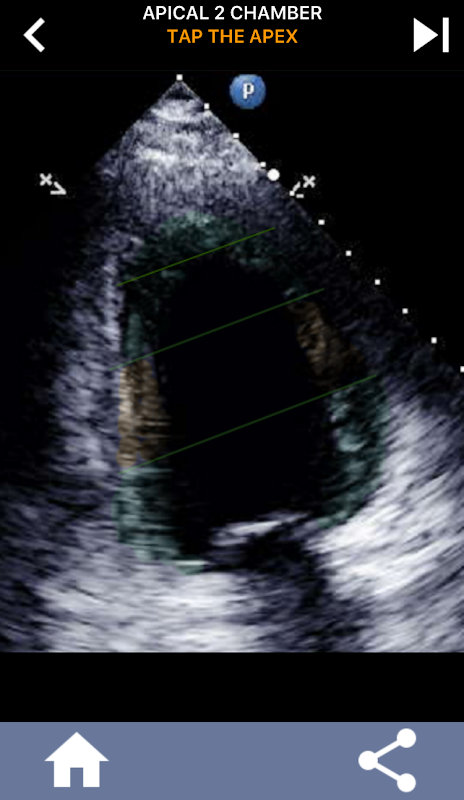

이 응용 프로그램은 AHA로 구분 된 심근을 보여주는 모든 반향보기를 포함하고 올바른 부분을 탭하도록 퀴즈 것입니다. 나는 개인적으로 빨리 반복적 인 퀴즈가 나를 위해 가장 잘 작동한다는 것을 알았다. 나는 주제를 빨리 배우고 암기해야한다. 당신이 에코 / TTE를 공부하는 초음파 학생이라면, 이것은 당신의 연구에 훌륭한 보완책이 될 것이라고 생각합니다.